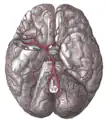

The arteries of the base of the brain

Cerebrum. Inferior view. Deep dissection.